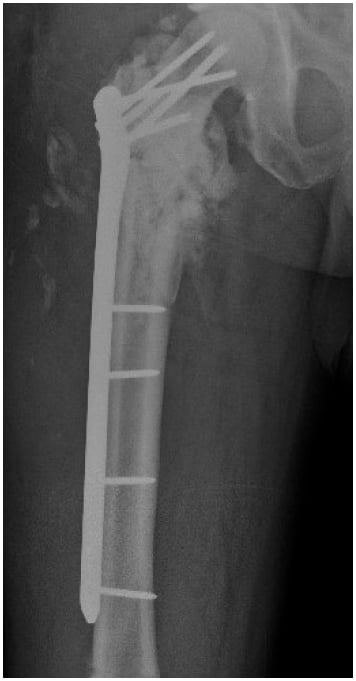

For the next year, the patient completed multiple rounds of antibiotics and underwent several more surgeries. In July 2021, he presented to the emergency department (ED) with persistent complaints of pain in the right hip and a sinus of draining purulence. Computed tomography (CT) revealed a right intertrochanteric fracture nonunion with well-circumscribed fluid collection (Fig. 2); the patient underwent open debridement, hardware removal, fracture stabilization, and antibiotic bead placement (Fig. 3). Deep cultures taken at this time revealed no bacterial growth. Of note, the patient had been maintained on dual antibiotic therapy for 8 weeks prior. Postoperatively, he was maintained on antibiotics and observed clinically and was discharged after 5 days.

Figure 3: X-rays after removal of the intramedullary nail show antibiotic beads and fracture fixation.